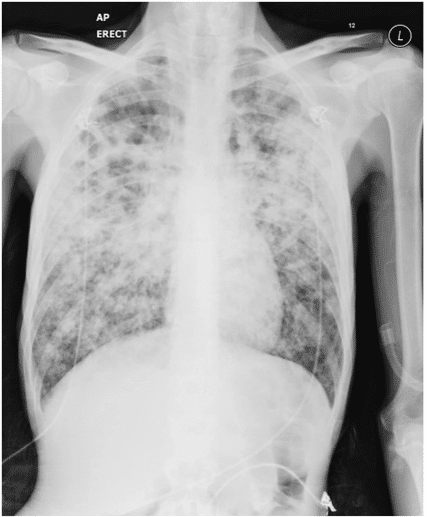

Diffuse nodular infiltration in HIV-TB coinfection in patient with CD4 count less than 200

Individuals with HIV are more prone to be infected with TB, a major cause of death for people with HIV. As HIV impairs the immune system, it is opportunistic for latent TB infection to turn into active TB disease. Without proper treatment, both HIV and TB can significantly shorten lifespan.

Unlike other HIV-associated opportunistic infections, tuberculosis may occur at relatively high levels of CD4 counts. However, its frequency markedly increases in patients with more severe immunosuppression. HIV-TB cases have been observed to have severe immunosuppression at presentation, with several studies reporting CD4 counts of less than 200.

In patients with mild immunosuppression, chest X-ray typically shows upper lobe or bilateral infiltrates, cavitation, pulmonary fibrosis, and shrinkage. The clinical picture often resembles post-primary pulmonary tuberculosis, and the sputum smear is usually positive.